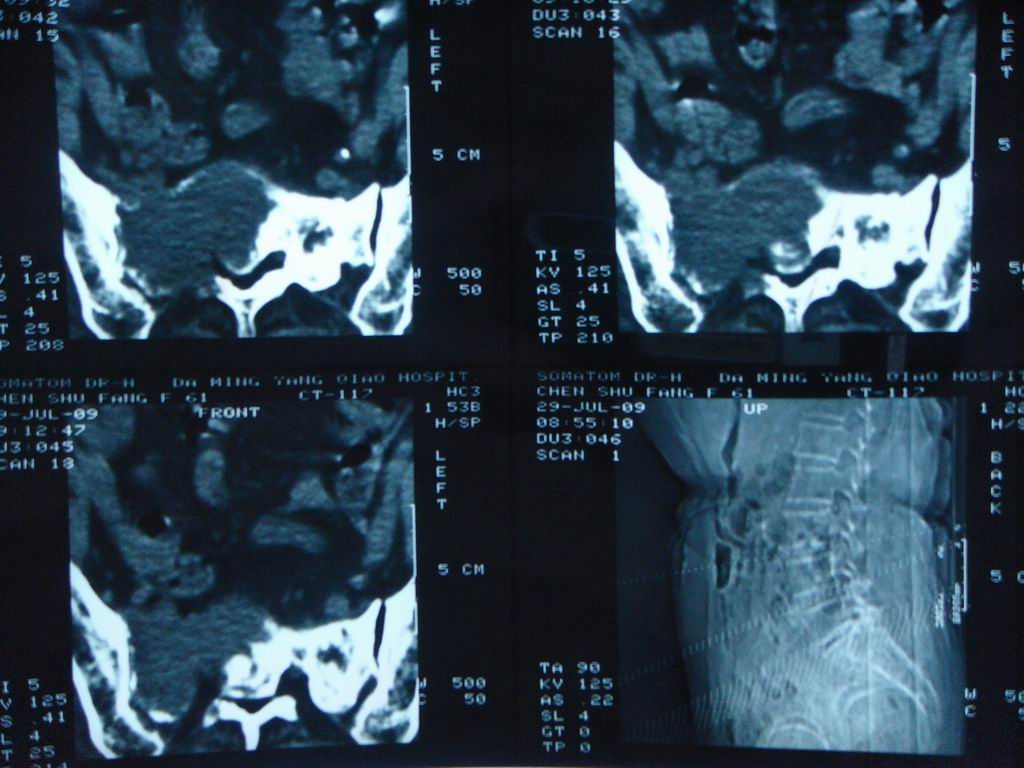

标题: CT21430:女性65岁 乳腺癌术后3年 [打印本页]

标题: CT21430:女性65岁 乳腺癌术后3年

结合病史,考虑骶骨转移瘤,但软组织肿块未突破骨壳,骨巨细胞瘤不能完全排除,骨髓瘤及脊索瘤不考虑。

结合病史,考虑骶骨转移瘤。

结合病史,考虑骶骨转移瘤。其它椎体,如腰5是否有问题呢?

个人感觉骨巨细胞瘤可能性大些。